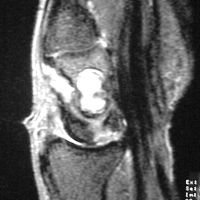

| MRI was

interpreted as inconclusive, differential including an

intraosseous cyst or giant cell tumor with cortical

thinning but no suggestion of malignancy. |